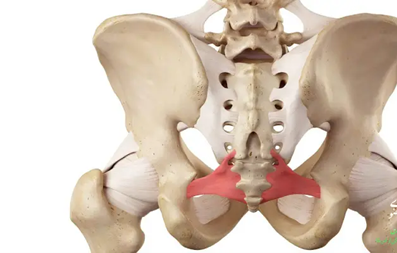

انواع شکستگی لگن

- شکستگی لگن معمولا در قسمت بلندی مفصل ران و در محل های مختلف اتفاق می افتد. گاهی اوقات سوکت یا ورق می تواند شکسته شود.

- شکستگی گردن فمور: این نوع شکستگی در استخوان ران در حدود 1 یا 2 اینچ اتفاق می افتد، جایی که سر استخوان به سوکت متصل می شود. شکستگی گردن فمورال ممکن است با ریختن عروق خونی، گردش خون را به توپ حامل خود برساند.

- شکستگی مفصلی: نوعی از شکستگی لگن است که شکستگی در ناحیه ای بین دو طرفه رخ می دهد.

- شکستگی داخل شکمی: این شکستگی قسمت های توپ و سوکت لگن شما را تحت تاثیر قرار می دهد. همچنین می تواند باعث انقباض عروق خونی که به توپ برود، منجر شود.